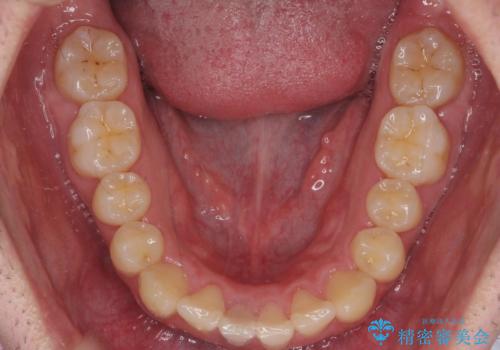

- 前歯のがたつきを主訴に来院。

歯を抜かずに、奥歯を後ろに下げ、歯の両側をわずかに削って並べました。

歯のがたつきがなくなると、歯ブラシがしやすくなり、茶色いステインも付きにくくなります。